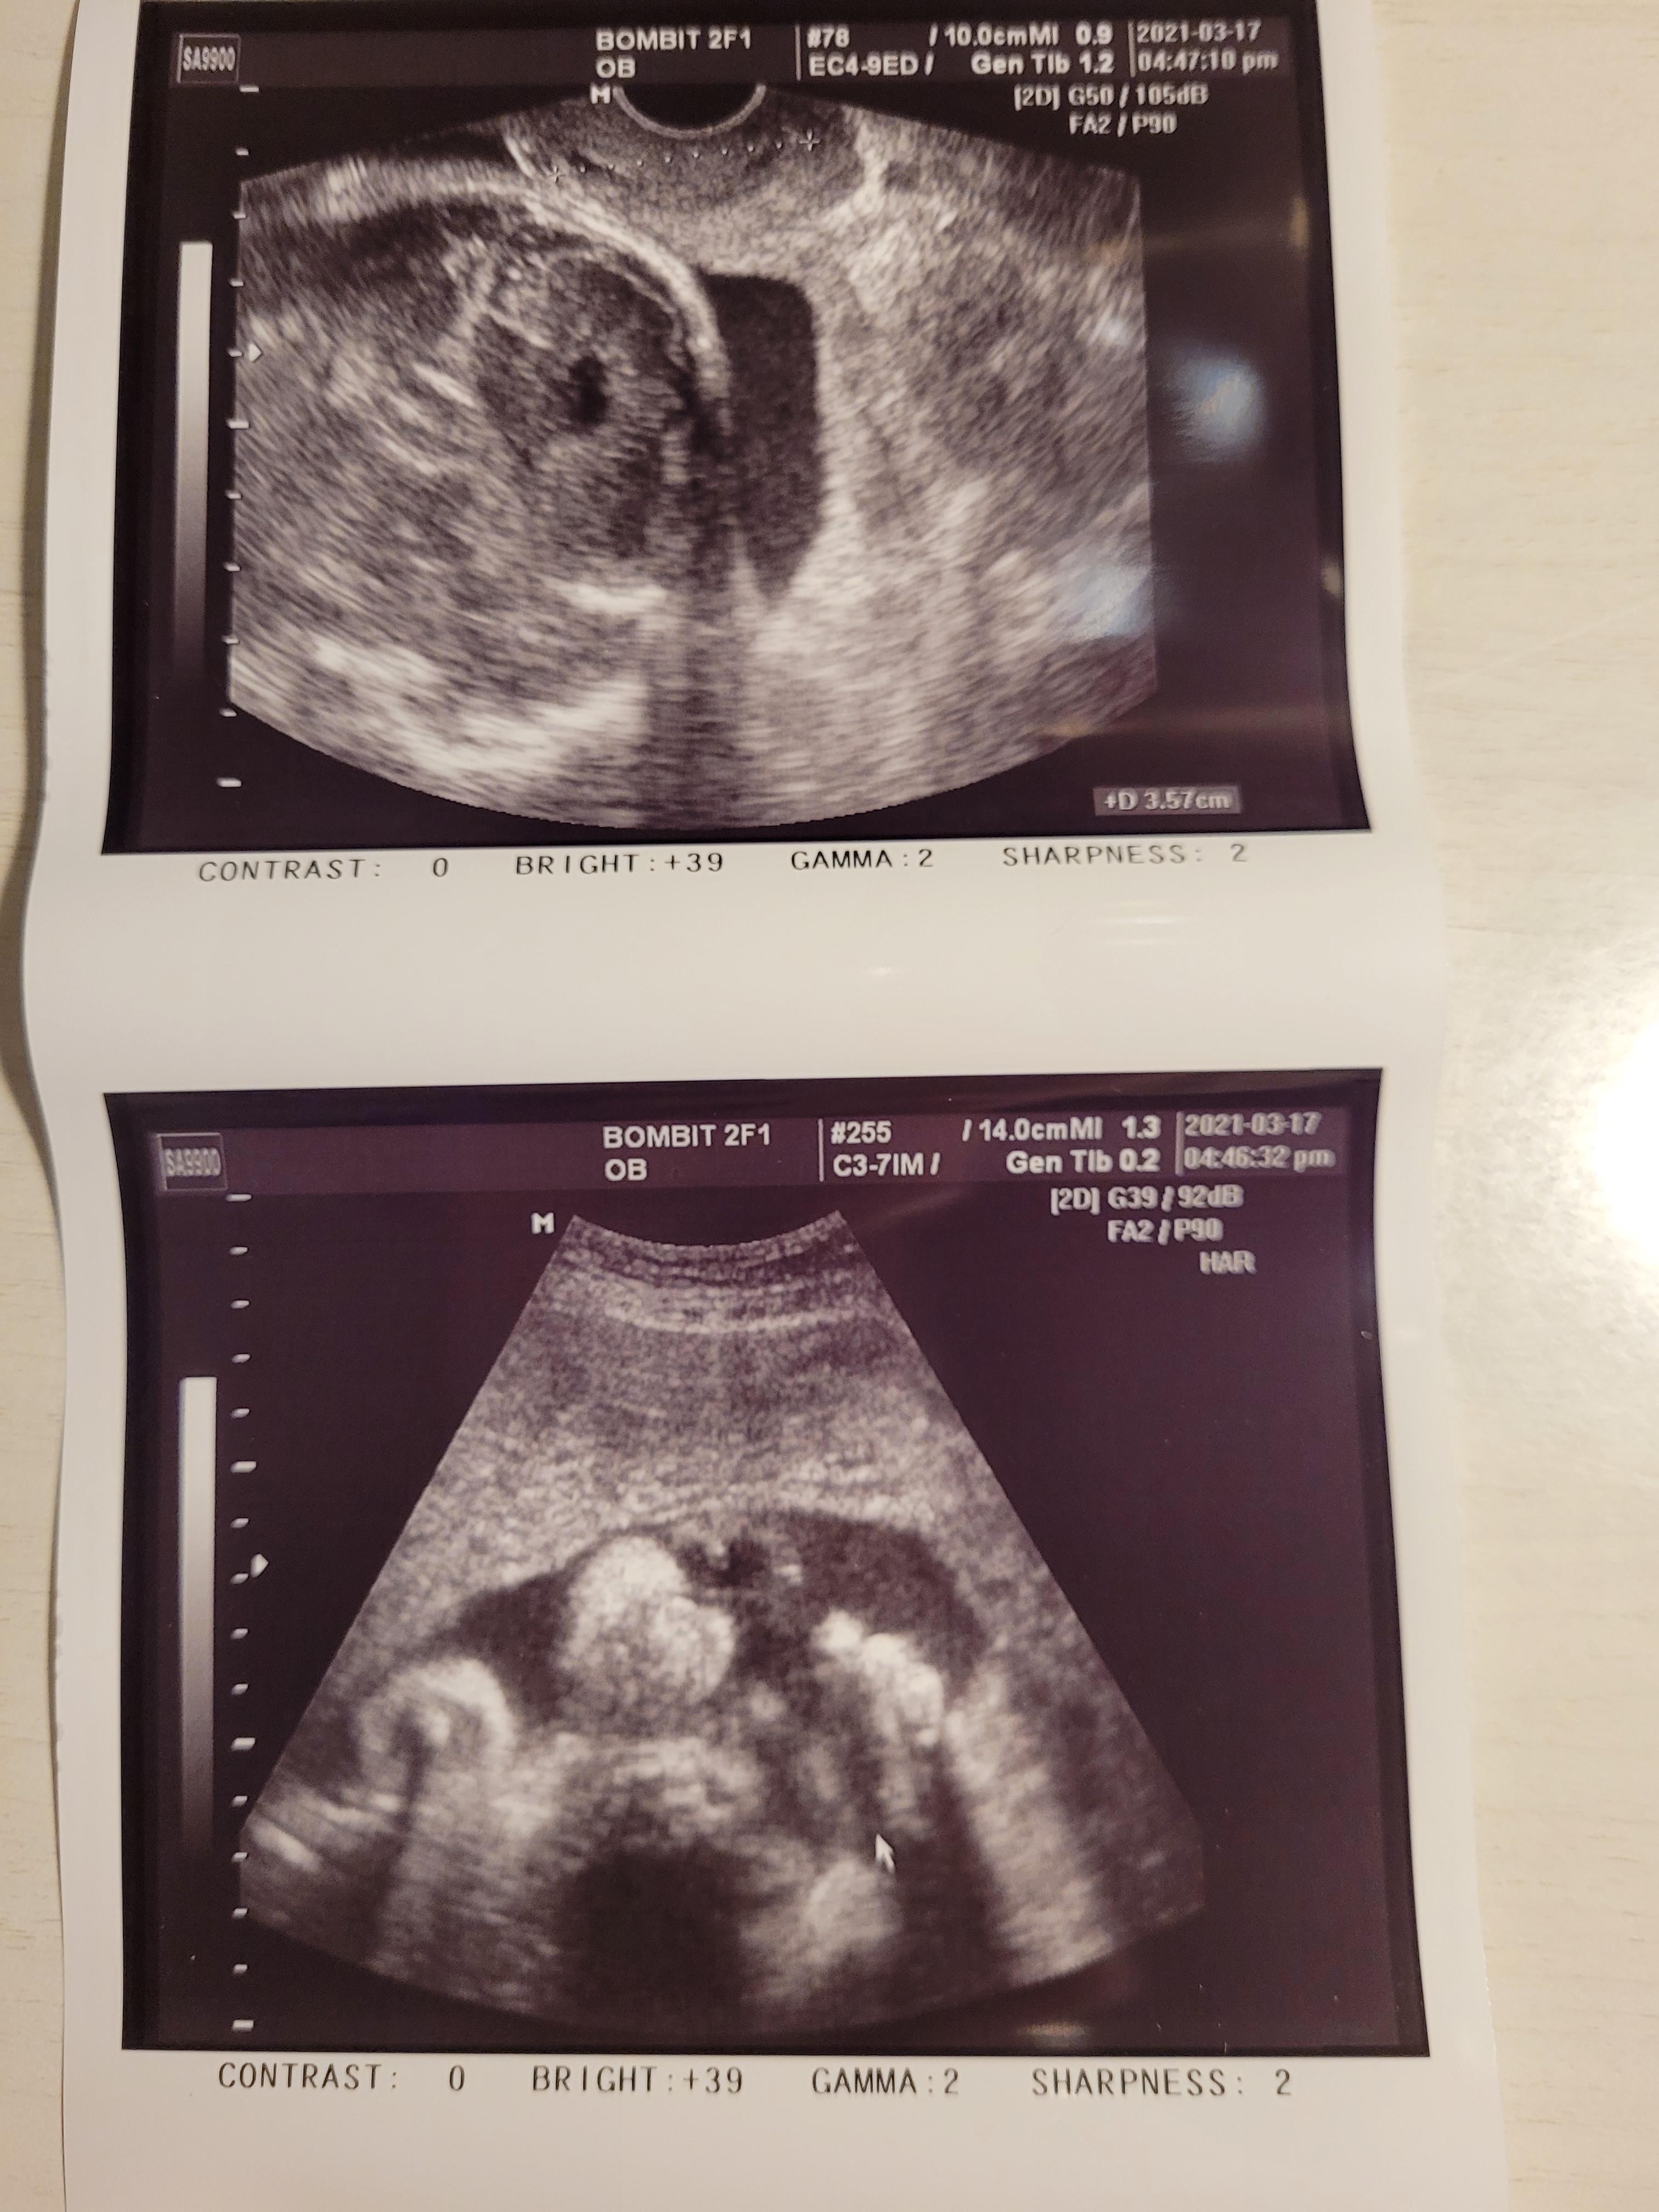

경부길이도 3.57cm로 짧은편은 아니어서 위험한 상황은 아니네요.

다만 경부가 얇아서 출산때까지 조심하기로했어요.